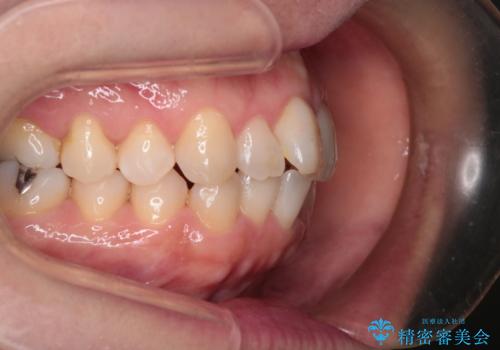

【インビザライン 】前歯のガタガタを治したい

- 前歯のガタガタを主訴に来院されました。

インビザライン で治療しました。途中は使用時間が20時間を切ることもありましたが、それでも頑張って使っていただき1年半で矯正終了することができました。